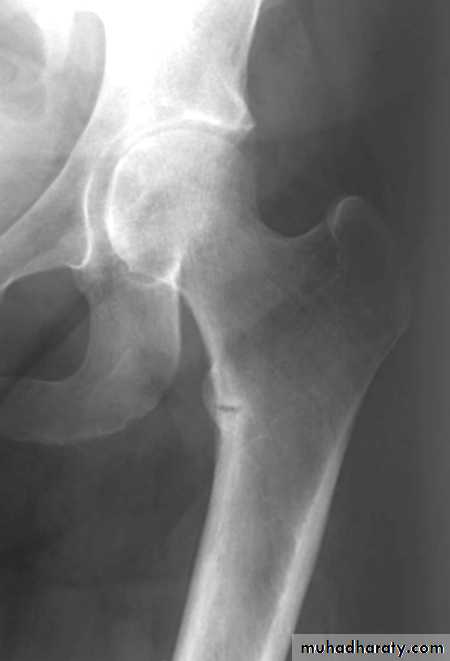

Wolff’s Law: Wolff’s Law is beautifully demonstrated

in the trabecular pattern at the upper end of the femur.The thickest trabeculae are arranged along the trajectories

of greatest stress.